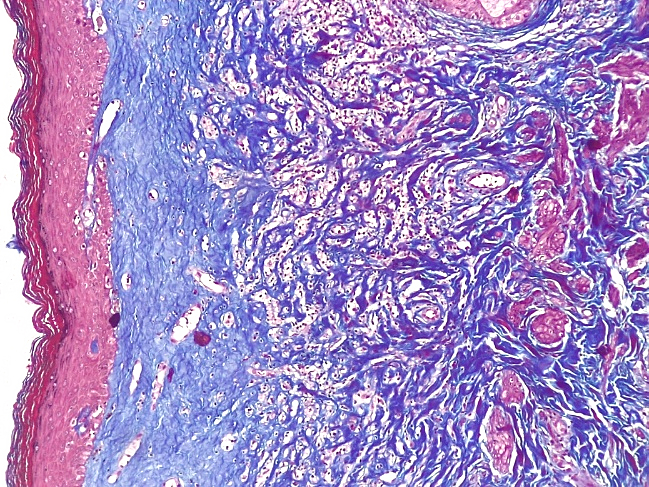

При проведении морфологического исследования тканей вульвы пациенток со склероатрофическим вариантом течения СЛВ также отмечалась резкая атрофия кожи за счет клеток эпидермиса и дермы, уменьшение клеточных слоев эпидермиса от 2–3 до 4–5 с участками повышенного ороговения (гипрекератоз). Количество базального слоя было снижено в разных случаях от 2–3 до 5–6 клеток в 1 мкм, что указывало на снижение функционального резерва эпидермиса. В случае длительного течения заболевания клетки базального слоя имели признаки дистрофии. В поверхностных слоях дермы отмечался фиброз с отложением масс гиалина, а также редукция кровеносных сосудов мелкого калибра, окруженных клеточным воспалительным инфильтратом из лимфоцитов и макрофагов (рис. 14–17).

В случае длительного течения склероатрофического варианта течения СЛВ отмечалось резко выраженное сдавление мелких кровеносных сосудов в поверхностных слоях дермы за счет фиброзной соединительной ткани с гиалинозом стромы (рис. 20).

Рис.19. Склероатрофический вариант течения СЛ. Резкая атрофия клеток эпидермиса, фиброз и гиалиноз поверхностных слоев дермы, склероз и перекалибровка сосудов мелкого калибра глубоких слоев дермы (окраска по Пикро-Маллори, х100)

Fig.19. Scleroatrophic variant of the course of SL. Sharp atrophy of epidermal cells, fibrosis and hyalinosis of the superficial layers of the dermis, sclerosis and recalibration of small-caliber vessels of the deep layers of the dermis (Picro-Mallory staining, x 100)